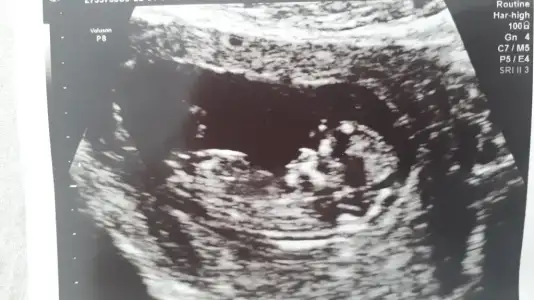

Ikra meyra Ikra meyra 11 haftalik bana da tahmin de bulunurmusunuz nub tam olarak neresi ben pek anlamadim :)

• BeautyPlus_20210409151800057_save.webp

BeautyPlus_20210409151800057_save.webp

28,1 KB · Görüntüleme: 64

• Screenshot_20210409-162230_Video Player.webp

Screenshot_20210409-162230_Video Player.webp

27,9 KB · Görüntüleme: 66